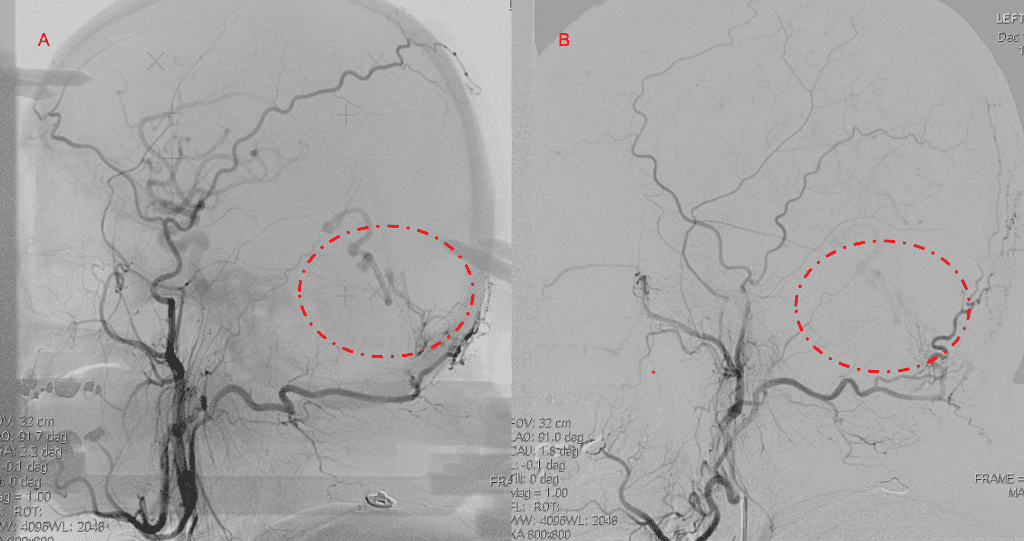

No severe neurologic deficits were observed initially. Her cerebral angiogram revealed a high flow Dural arterial venous fistulous malformation of the tentorium supplied by the bilateral external carotid and left vertebral arteries into a large venous varix within the fourth ventricle at the site of the hemorrhage. Deep venous drainage is observed into the Galenic and Straight Sinus of the posterior fossa (Figure 2).

Figure 2. [A] Ruptured Varix/Aneurysm of the Deep Venous Posterior Fossa drainage and AV shunting (arrows) [B] Posterior Meningeal Artery Fistula [C] Right Middle Meningeal Artery Fistula [D] Post embolization Left Vertebral Angiogram demonstrates resolution of the high flow and pressure A-V Shunting following successful embolization with liquid embolic (NBCA).